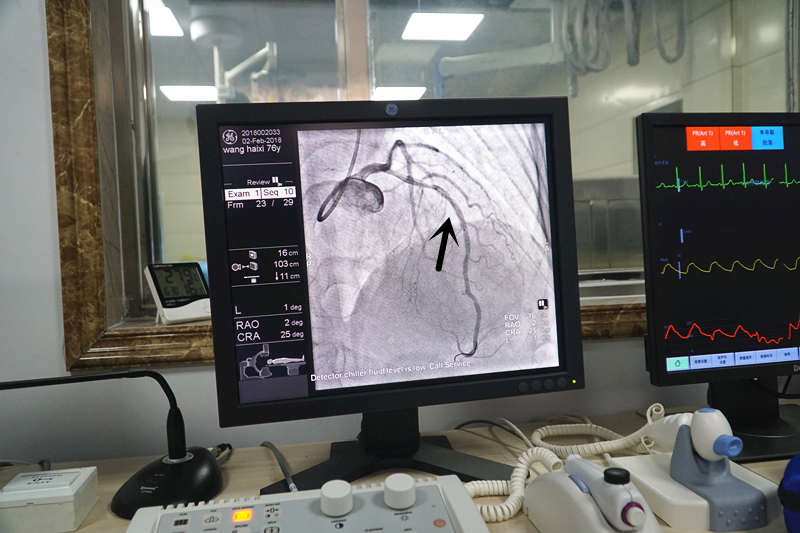

心臟血管支架成功植入,管腔血流恢復(fù)通暢。